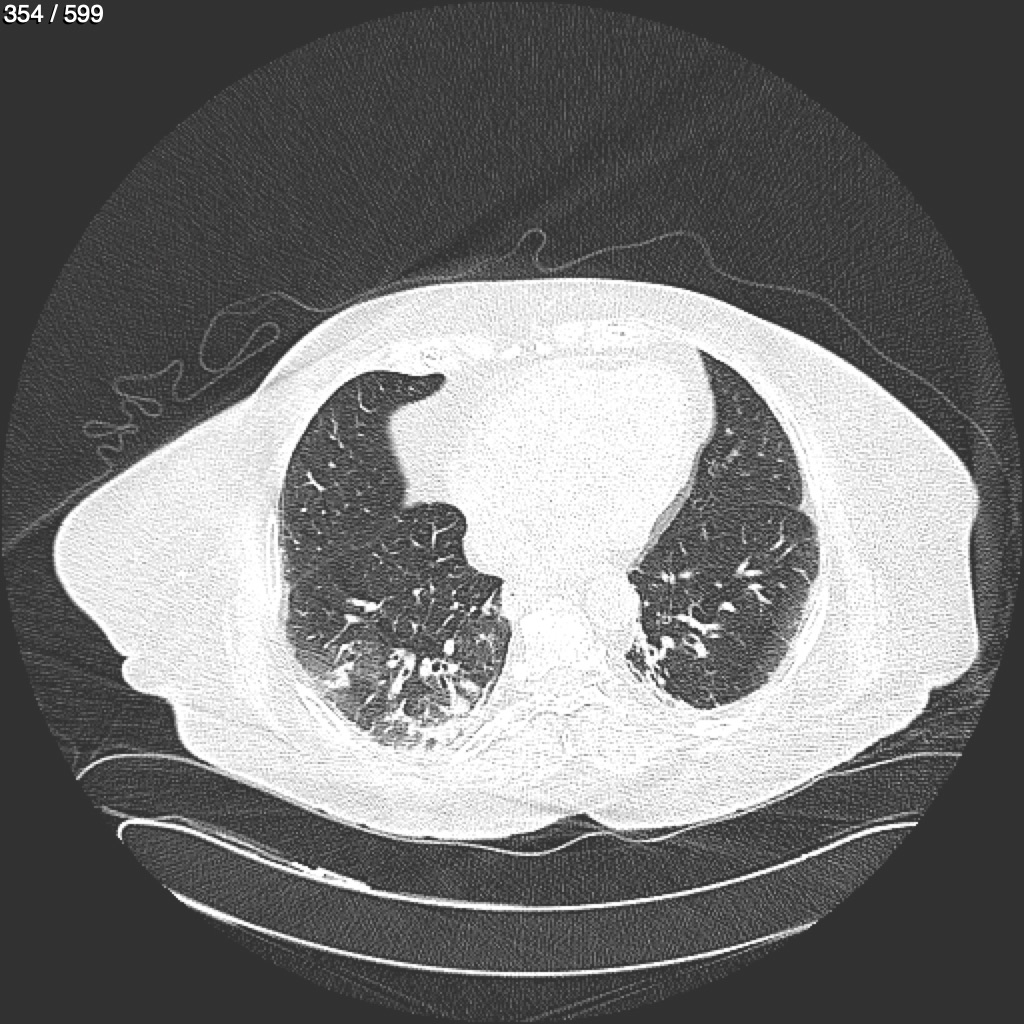

Home G​l​o​r​i​a​ ​G​l​a​d​y​s​ ​B​e​a​s​l​e​y​ ​-​ ​T​ó​r​a​x​ ​T​o​r​a​x​_​S​i​m​p​l​e​ ​(​A​d​u​l​t​o​)